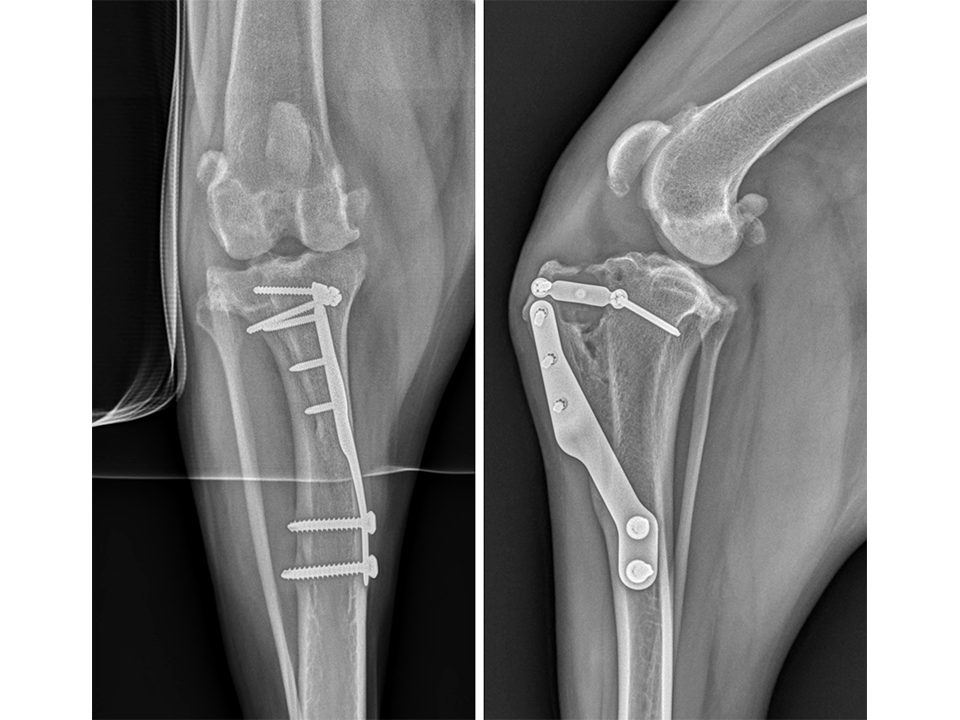

Immediate postoperative radiographs (Fig 7) revealed satisfactory implant and osteotomy positioning. Radiographs obtained 10 weeks postoperatively (Fig 8) showed no evidence of implant-associated complications and partial bone healing within the osteotomy gap. Osteoarthritic changes within the joint were static. Clinically at this stage, mild bilateral pelvic limb lameness was apparent bilateral stifle joint effusion. The left stifle joint was stable in CrTT with no pain response upon stifle joint manipulation.